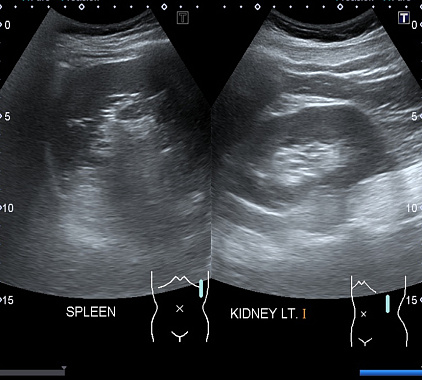

Фотогалерея

Оборудование УЗИ